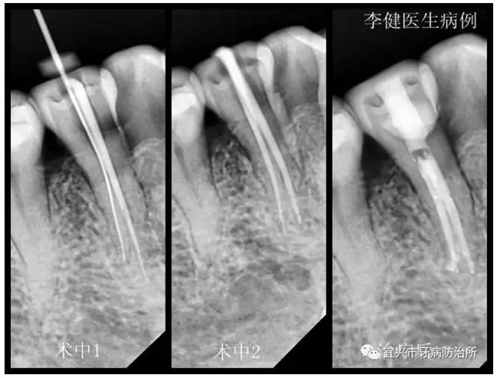

患者,女,55歲,右下前磨牙繼發(fā)齲伴自發(fā)性疼痛前來就診,X線片顯示為雙根管。術(shù)中1選用鎳鈦根管預(yù)備銼第一次根管預(yù)備未找到,后選用8號(hào)細(xì)銼在根中1/3處找到另一根管,拍X線片確認(rèn)。術(shù)中2再次用鎳鈦根管銼預(yù)備,并用次氯酸鈉溶液反復(fù)沖洗根管。最后利用超聲振蕩機(jī)蕩洗根管后,用熱牙膠系統(tǒng)嚴(yán)密充填根管,并用樹脂充填窩洞。待后期烤瓷冠修復(fù)。

來源:宜興市牙病防治所